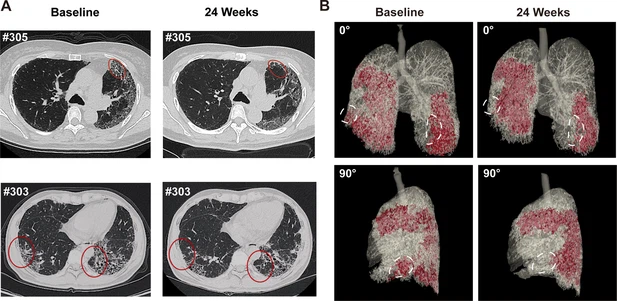

• 蜂窩狀病變消退:1M劑量組中兩名患者(#303、#305)的HRCT顯示下葉蜂窩狀病變減少(圖4A),三維重建證實(shí)下葉病變區域縮?。▓D4B)。

圖4:REGEND001治療前后的代表性肺部CT圖像。

(A) 患者#305和#303在基線(xiàn)和REGEND001治療后24周的代表性肺部CT圖像。紅色圓圈表示蜂窩狀病變消退。(B) 患者#305連續CT圖像的三維可視化。紅色區域表示細胞治療前后肺部受損區域(網(wǎng)狀和蜂窩狀)。白色圓圈表示下葉病變消退。

總結:REGEND001高劑量治療可顯著(zhù)改善IPF患者運動(dòng)能力及生活質(zhì)量,并在部分患者中實(shí)現肺纖維化結構的可逆性修復(尤其下葉)。療效呈現劑量依賴(lài)性,且與細胞分布機制相關(guān)。盡管樣本量有限,但結果為再生療法逆轉肺纖維化提供了首個(gè)影像學(xué)證據,需擴大隊列驗證長(cháng)期效果及機制。